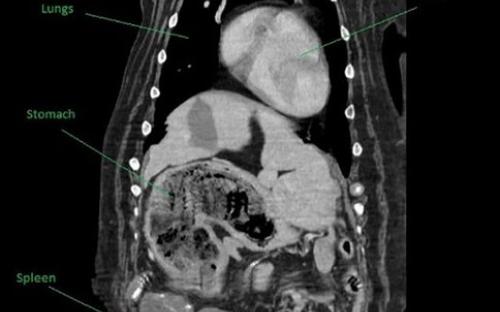

Но оказалось, что все далеко не так страшно, как подумали ветеринары, изучив снимки внутренних органов. На самом деле у Мейзи не было никакого рака: она каким-то образом проглотила четыре плюшевых игрушки, которые и вызывали проблемы в организме.

Хотя достать их было непросто, сама операция получилась куда безопаснее, чем если бы у сенбернара был рак. По словам ветеринара Ника Блэкберна, они с коллегами никак не ожидали, что найдут в животе у собаки игрушки.